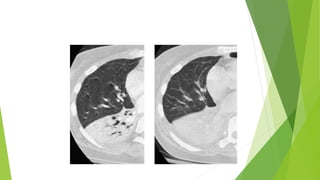

Tomografía computarizada

 Es mucho más fácil de ver en

TC y su presencia permite

asegurar que la lesión es

intrapulmonar

 Bronquios periféricos visibles en

la mayor parte del campo

pulmonar

Tomografía computarizada  Esmucho más fácil de ver en TC y su presencia permite asegurar que la lesión es intrapulmonar  Bronquios periféricos visibles en la mayor parte del campo pulmonar